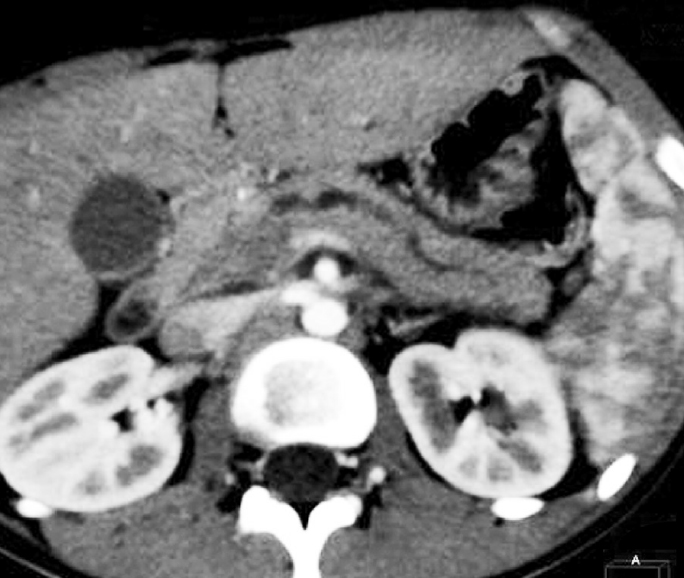

КТ (контроль): при сопоставлении с данными предыдущей МСКТ положительная динамика — уменьшилась степень расширения вирсунгова протока до ~3 мм (ранее ~5 мм). Отмечается также уменьшение размеров ПЖ в области тела и хвоста (13 × 15 мм соответственно). Перестали прослеживаться инфильтрация в парапанкреатической клетчатке и скопление жидкости в этой области. Сохраняется увеличение головки ПЖ до 30 × 40 мм (нельзя исключить уменьшения на 1–2 мм). Структура ее неоднородная, с более плотными участками (до 45 HU в сравнении с остальными отделами 40 HU).

Контуры железы мелкофестончатые. Контрастирование своевременное, достаточно гомогенное, диаметром до 14 мм.

Заключение: КТ-картина увеличения размеров и неоднородности структуры ПЖ в области головки. Положительная динамика в сравнении с данными предыдущей МСКТ (рис. 4).

Рис. 4. Магнитно-резонансная холангиопанкреатография ребенка с аутоиммунным панкреатитом в динамике на фоне лечения: размеры холедоха и вирсунгова протока уменьшились

Fig. 4. Magnetic resonance cholangiopancreatography of a child with AIP in dynamics during treatment: the size of choledochous and Wirsung’s ducts has diminished